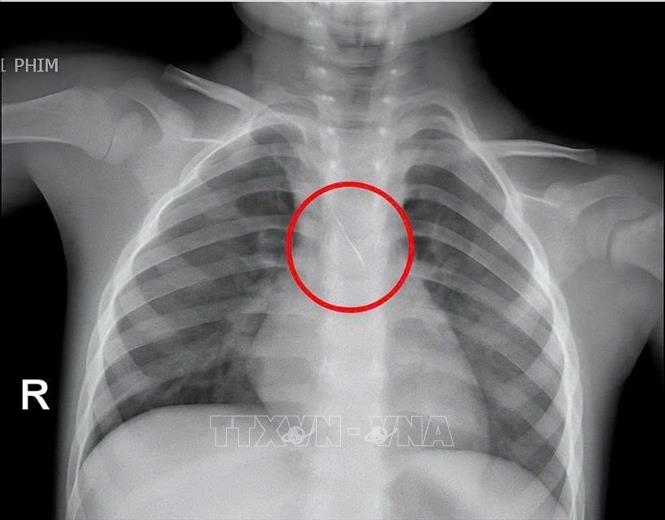

Hình ảnh chiếc kim chọc tuỷ rơi vào trong đường thở của bé trai 3 tuổi. Ảnh: TTXVN phát

Sáng 15/11/2025, Bệnh viện Đa khoa tỉnh Quảng Trị cho biết, đơn vị vừa gắp thành công dị vật cho 1 bé trai bị kim chọc tủy dài 22mm vào đường thở khi đi làm răng. Đây là trường hợp hi hữu có thể gây hậu quả rất nặng như xẹp phổi, viêm phổi, áp xe phổi, tràn khí màng phổi hoặc tử vong nếu không xử trí kịp thời. Cụ thể, trước đó, đơn vị tiếp nhận bé N.Q.T.Đ (3 tuổi), trú tại xã Cửa Việt, trong tình trạng ho nhiều, ho sặc. Kết quả chụp phim cho thấy một dị vật kim loại dài khoảng 22mm nằm ở góc carina, vị trí chia đôi khí quản, đe dọa gây tắc nghẽn đường thở. Ngay lập tức, bệnh viện tiến hành hội chẩn liên khoa và quyết định nội soi phế quản cấp cứu. Dị vật được phát hiện với một đầu nhọn cắm vào 1/3 dưới khí quản, đầu còn lại nằm trong phế quản gốc trái được xác định rất nguy hiểm. Sau 15 phút thao tác khẩn trương, dị vật được lấy ra an toàn. Bé trai cải thiện triệu chứng ngay sau can thiệp và xuất viện sau 48 giờ theo dõi. Theo thông tin từ gia đình bệnh nhi, bé N.Q.T.Đ khi đang làm răng thì kim chọc tủy bất ngờ rơi từ khoang miệng xuống đường thở của trẻ../.Ảnh: TTXVN phát